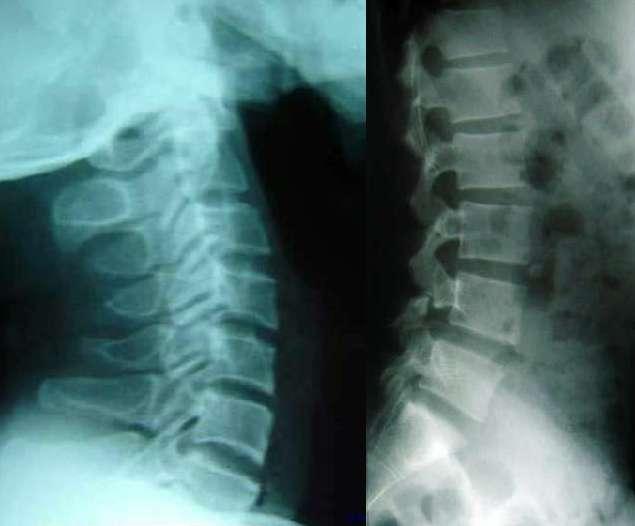

X-Quang của bệnh nhân loãng xương. Ảnh: BSCC